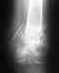

Перелом локтевого отростка, МОС 28.11.19. Снят гипс 27.12.19. Не разрабатывается рука. В чем причина, непонятно.

Угол сгибания локтя примерно 110-150 гр., с момента снятия гипса прогресса практически нет (ЛФК ежедневно,несколько раз в день). Встал вопрос, возможно, рука больше и не согнется пока пластина внутри? Или же, нужно просто больше времени?Буду очень благодарна за ответы

• Кликните для загрузки файла Снимок боковой1.jpg